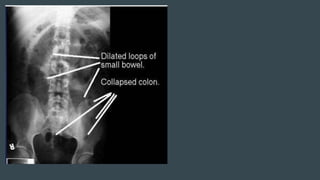

RADIOLOGICAL PICTURE

Small Bowel Obstruction

Central distention (GAS)

Valvulae conniventes

Ladder-like dilatation

Small diameter

In most cases, the abdominal

radiograph will have the following

features:

1. Dilated loops of small bowel

proximal to the obstruction

2. predominantly central dilated

loops

3. dilatation of loops over 3cm

4. valvulae conniventes are visible

RADIOLOGICAL PICTURE Small BowelObstruction Central distention (GAS) Valvulae conniventes Ladder-like dilatation Small diameter Large Bowel Obstruction Peripheral distention “Picture frame” More gross distention Haustral indentation & large diameter

In most cases,the abdominal radiograph will have the following features: 1. Dilated loops of small bowel proximal to the obstruction 2. predominantly central dilated loops 3. dilatation of loops over 3cm 4. valvulae conniventes are visible